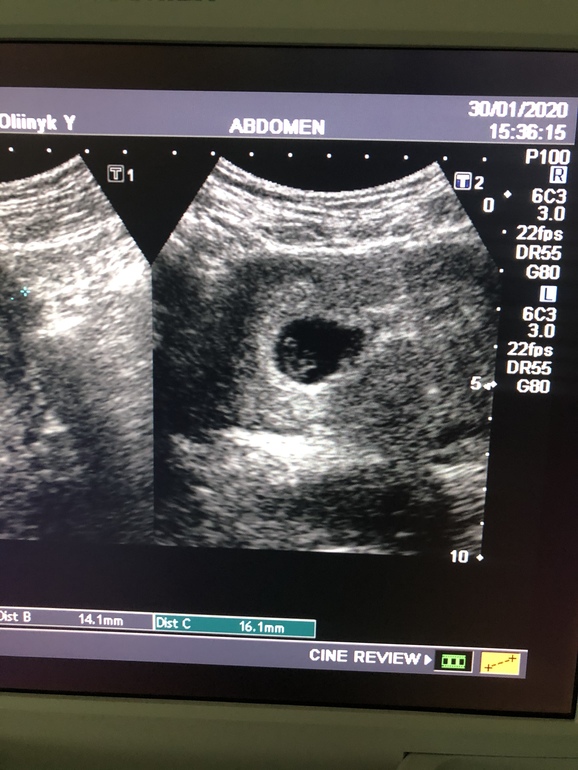

УЗИСегодня ровно 8 недель беременности)))

Ночью тянуло живот , аж 2 таблетки ношпы выпила. Сходила на узи - ЧСС:174 уд/ мин .

Но толи узи аппарат неочень, толи узист- он почему-то ПЯ посчитал всего 18 мм.

Малыш там маленький и очень нечетко все было видно ( думаю все таки аппарат старый), но главное что сердечко бьется)))

Узи по животу .